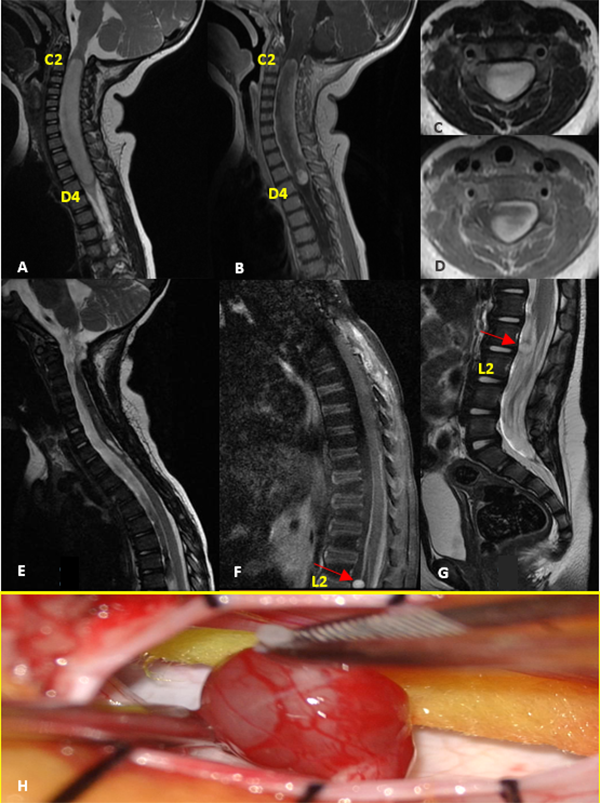

V: Ependimoma

Paciente sexo masculino con NF2 que comienza a los 7 años con cervicalgia de 2 meses de evolución refractaria a analgésicos evidenciando en la RM un tumor intramedular cervical (C2-C7) con realce post contraste y el “signo del gorro” típico de ependimoma. Se realizó exéresis completa de la lesión demostrado en la RM control. El monitoreo intraoperatorio mostró caída de la onda D cercana al 50%. El McCormick postoperatorio inmediato fue grado 3. A los 6 meses de seguimiento con rehabilitación se evidenció mejoría clínica con McCormick grado 1. La anatomía patológica informó ependimoma clásico. Posteriormente el paciente evolucionó con progresión de su enfermedad de base, con lesiones intracreneales que requirieron tratamiento quirúrgico y radiocirugía. Casi 6 años después de la resección del ependimoma cervical, presentó recidiva local (C3-C4) y aumento considerable de una lesión a nivel de C1-C2 intra-extradural que se controlaba con imágenes seriadas. Se realizó la exéresis completa de ambas lesiones en un mismo acto quirúrgico, cuya anatomía patológica reveló schwannoma para el tumor extramedular y ependimoma clásico con Ki67 de 6% para la lesión intramedular. Como complicación alejada presentó dehiscencia de la herida, que requirió cierre quirúrgico (Figura 5).

Figura 5: Ependimoma. A-B: RM prequirúrgica T1 con contraste y T2 cortes sagitales. C-D: Imágenes intraoperatoria pre y postresección. E-F: RM postquirúrgica T1 con contraste y T2 cortes sagitales.